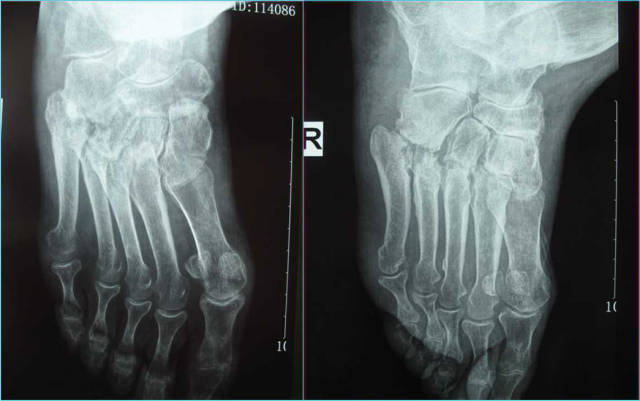

影像学所见:第3-5跖骨基底部骨质改变,第3跖骨与外侧楔骨的关节、第4、5跖骨与骰骨之间的关节明显受累。

诊断:右足跖跗关节破坏

启示:从影像上看患者是一个Lisfrank关节破坏,但究竟是什么原因导致的呢?为了能够尽快的解决谭某行走疼痛,我院专家组今日针对谭某的病情进行了讨论。2年前在外院进行了多次检查及治疗后,效果并不是很明显,与今年来我院再次接受治疗,通过我院的一些列检查得知谭某的Lisfrank关节破坏的原因不排除骨关节炎或类风湿性关节炎、血清阴性脊柱关节病、结晶相关性关节炎。